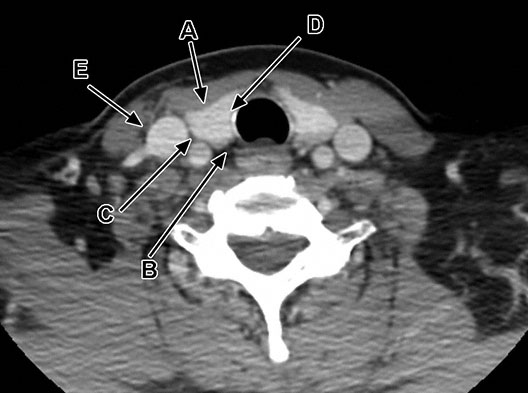

A 58-year-old woman comes to the physician because of a 6-month history of fatigue and muscle weakness. Physical examination shows no abnormalities. Serum studies show a calcium concentration of 11.8 mg/dL and intact parathyroid hormone concentration of 340 pg/mL. A nuclear parathyroid scan is shown; the arrow indicates a parathyroid adenoma in the region of the right lower pole of the thyroid gland. This adenoma is most likely located in which of the following labeled areas of the axial CT scan of the thyroid gland?